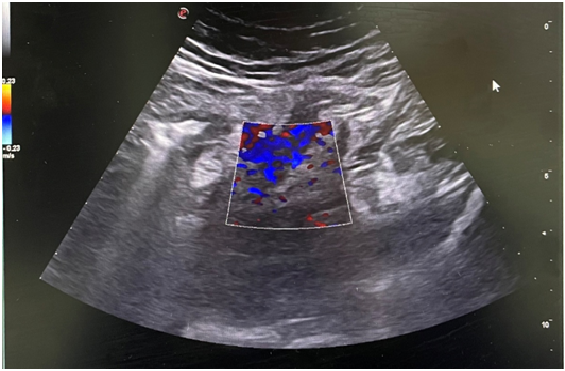

Juicio clínico, diagnóstico diferencial, identificación de problemas

Ante la sospecha de apendicitis aguda se deriva al paciente a Urgencias hospitalarias para ser valorado por el Servicio de Cirugía, donde se vuelve a realizar ecografía de abdomen y se observa, apéndice veriforme en FID, calibre hasta 12 milímetros, con ligeros cambios inflamatorios en el mesoapéndice y flogísticos en Doppler color, asociado a Blumberg ecográfico. (Imagen 2)